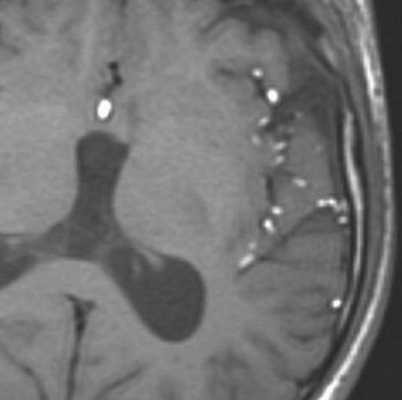

Кисты сосудистого сплетения относятся к редким патологиям, обнаруживаемым случайно при МРТ или КТ головного мозга. Кисты в области сосудистого сплетения могут в норме наблюдаться у плода, но исчезают к 26 неделе беременности. Считается, что часть случаев связано с трисомией 18 хромосомы.

При КТ видна характерная кальцификация по краям кисты. При МРТ головного мозга киста представляет собой мелкие четко очерченные ликворные образования. Дифференциальную диагностику при МРТ головного мозга надо проводить с :

Ксантогранулема при МРТ головного мозга очень похожа на кисту сосудистого сплетения, но отличается смешанным содержимым из жира, коллоида, ликвора и продуктов крови. По этой причине на МРТ типа FLAIR они остаются видны. На диффузионно-взвешенных МРТ сигнал от ксантогранулемы яркий, в отличие от кист.

Гипертрофия сосудистого сплетения видна на МРТ головного мозга как его диффузное увеличение, нередко приводящее к гидроцефалии. Плексит - воспалительный процесс, сопровождающийся воспалением и гипертрофией сосудистого сплетения и сочетающийся с вентрикулитом и церебритом, именно их проявления, в первую очередь видны при МРТ головного мозга.